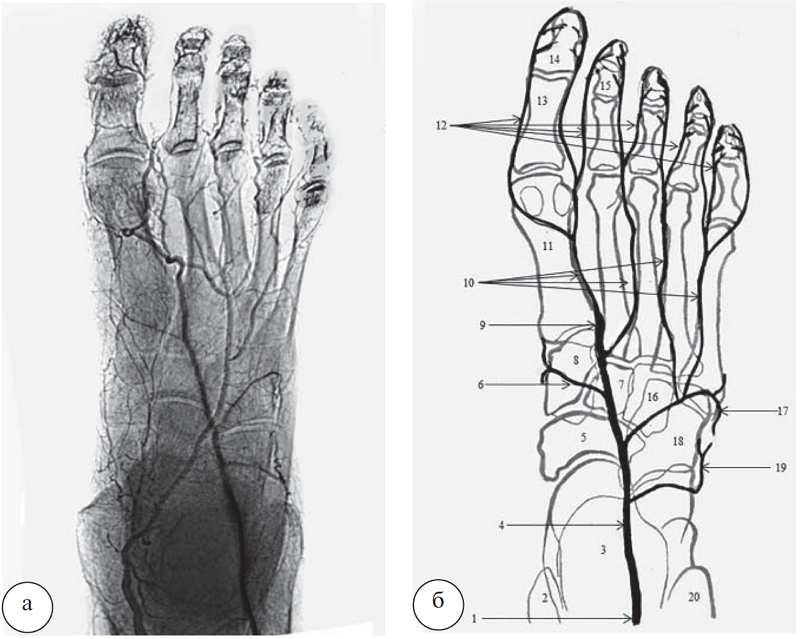

При прямой укладке ТАС проецируется на передней поверхности большеберцовой кости по середине между лодыжками. В 32 наблюдениях обнаружен вариант архитектоники тыльной артерии стопы, описанный в учебниках и атласах по анатомии человека (рис. 2).

Рис. 2. Вариант прямолинейной архитектоники ствола ТАС: а – ангиорентгенограмма; б – схема ТАС и ее ветвей (подошвенные артерии на схеме отсутствуют). 1 – передняя большеберцовая артерия; 2 – медиальная лодыжка; 3 – таранная и пяточная кости; 4 – тыльная артерия стопы; 5 – ладьевидная кость; 6 – медиальная предплюсневая артерия; 7 – промежуточная клиновидная кость; 8 – медиальная клиновидная кость; 9 – глубокая подошвенная ветвь; 10 – тыльные плюсневые артерии; 11 – I плюсневая кость; 12 – тыльные пальцевые артерии; 13 – проксимальная фаланга I пальца; 14 – дистальная фаланга I пальца; 15 – средняя фаланга II пальца; 16 – латеральная клиновидная кость; 17 – дугообразная артерия; 18 – кубовидная кость; 19 – латеральная предплюсневая артерия; 20 – латеральная лодыжка

При данном варианте ТАС имеет прямолинейный ход. От места своего начала она направляется к первому межкостному плюсневому промежутку, пересекая в косом направлении проекции костей предплюсны. ТАС проецируется на латеральный край головки таранной кости, затем на латеральный край ладьевидной кости, переходит по середине проекции промежуточной клиновидной кости и у латерального края первой плюсневой кости, на границе ее тела и основания продолжается в глубокую подошвенную ветвь. Последняя анастомозирует с латеральной подошвенной артерией. На всем протяжении просвет основного ствола артерий существенно не меняется, а глубокая подошвенная ветвь по своему диаметру равна диаметру конечной ветви латеральной подошвенной артерии. Следовательно, ТАС играет важную роль в кровоснабжении дистального отдела подошвы. В месте ответвления глубокой подошвенной ветви от ТАС отходит первая тыльная плюсневая артерия, которая по направлению является продолжением ТАС и тянется вдоль латерального края первой плюсневой кости. На уровне головки первой плюсневой кости от нее ответвляются тыльные пальцевые артерии к первому и второму пальцам.

В области медиального края основания второй плюсневой кости от ТАС ответвляется вторая тыльная плюсневая артерия, которая во втором межкостном плюсневом промежутке направляется к пальцам. В проекции середины промежуточной клиновидной кости от ТАС отходит медиальная предплюсневая артерия, которая направляется вперед и медиально и разветвляется на медиальной поверхности предплюсны.

На уровне латерального края головки таранной кости от ТАС берет свое начало латеральная предплюсневая артерия, которая отдает многочисленные ветви к латеральной поверхности предплюсны. В проекции латерального края ладьевидной кости от ТАС отходит дугообразная артерия, которая направляется в латеральном направлении и достигает основания пятой плюсневой кости. В этом месте дугообразная артерия делится на две самостоятельные тыльные плюсневые артерии, которые проходят вдоль боковых поверхностей четвертой и пятой плюсневых костей и делятся на пальцевые артерии.